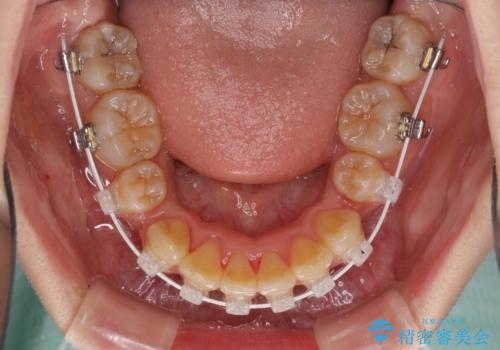

- 矯正装置

- 審美装置

- 治療計画

- 口元の閉じにくさと、前歯のでこぼこの歯並びを気にして来院された患者様です。

口元を積極的に引っ込めるために、上下左右の小臼歯計4本を抜歯することとしました。

咬み合わせが深く、咬合力強いため、補助装置を使用しながら積極的に口元を下げることとしました。

矯正治療終了近くに九州へ引っ越すことになってしまい、なかなか来院することができなくなったため、引っ越してから1年以上の期間が必要となってしまいました。